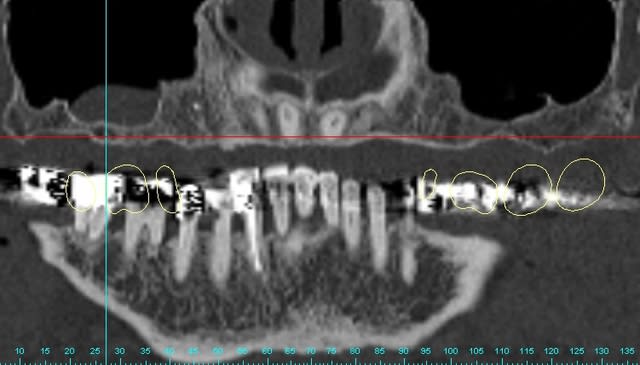

pour votre plaisir mon ami 8 mois d'écarts

fenêtre fermée par du vitalos pas de membrane technique "grosse ouverture"

Gar cross section1 tgeo1t - Eugenol

Gar cross section2 aw0gxu - Eugenol

Garaxial1 az74ic - Eugenol

Gart axial2 veeu9c - Eugenol

Gart panoramic1 ssmlda - Eugenol

Gart panoramic2 isuhmz - Eugenol